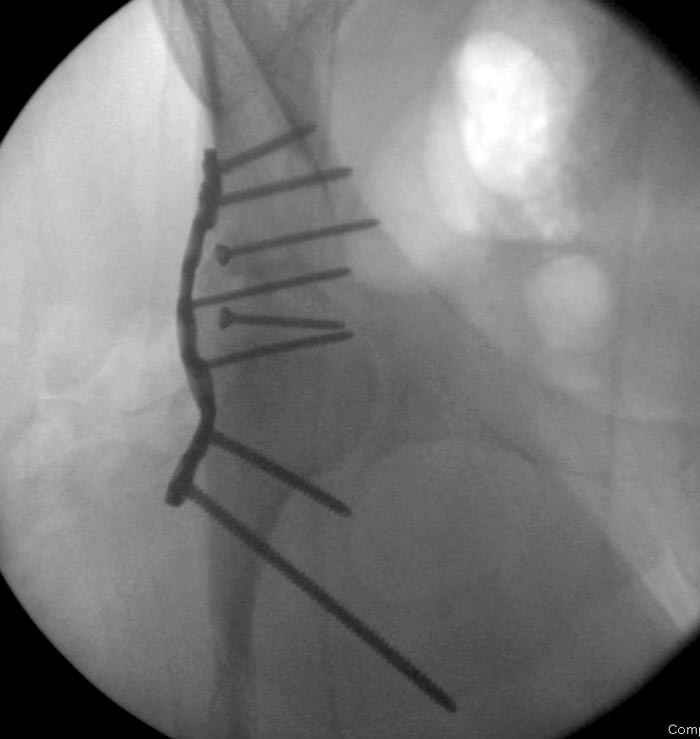

Интраоперционные N5 косая запирательная и N6 подвздошный снимок

11:50 больной в послеоперационной, рентгенограмма N7, компьютерная томограмма в тот же день N8-10